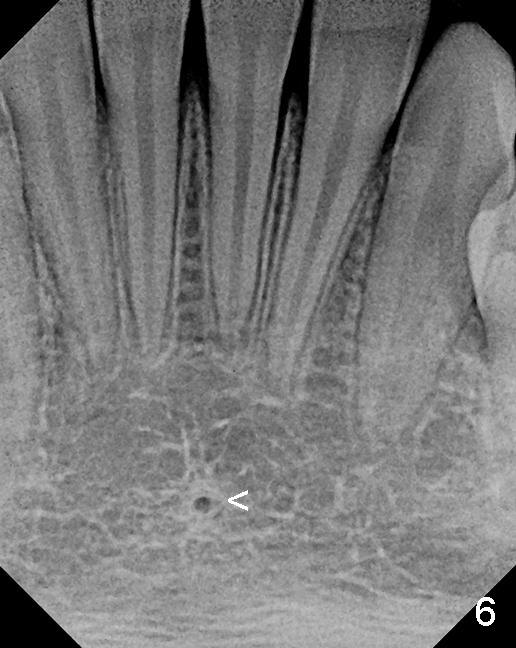

舌动脉(Lingual artery)是颈外动脉(External carotid artery)第二个前分支(图一),舌动脉末分支是舌下动脉(Sublingual artery)。舌动脉行于下颌骨舌侧(图二),它末分支舌下动脉中止于下颌骨切牙舌侧(图三),舌下动脉与颏下动脉(Submental artery,面动脉(Facial artery)分支)有吻合(箭头)。下颌骨舌侧有多个小孔(图四):正中(a, d),侧(c, e)舌孔,主要动脉穿入(1)。全景片(图五),前牙根尖片(图六)可显示舌孔(箭头, Lingual foramen)。舌孔延伸下颌骨舌侧一半(图七),下前牙植牙造成严重出血(图十,十一,2),往往是因为舌侧骨板穿孔,研究表明牙槽骨萎缩是血管意外(舌侧骨板容易破裂)主要因素(3,图八a,图九),预防方法:术前下颌骨舌侧触诊,对危险性大的病例做CT检查;术中钻洞时做下颌骨舌侧触诊,对危险性大的病例,翻瓣,暴露舌侧骨板,保护舌侧结构,使用短种植体。